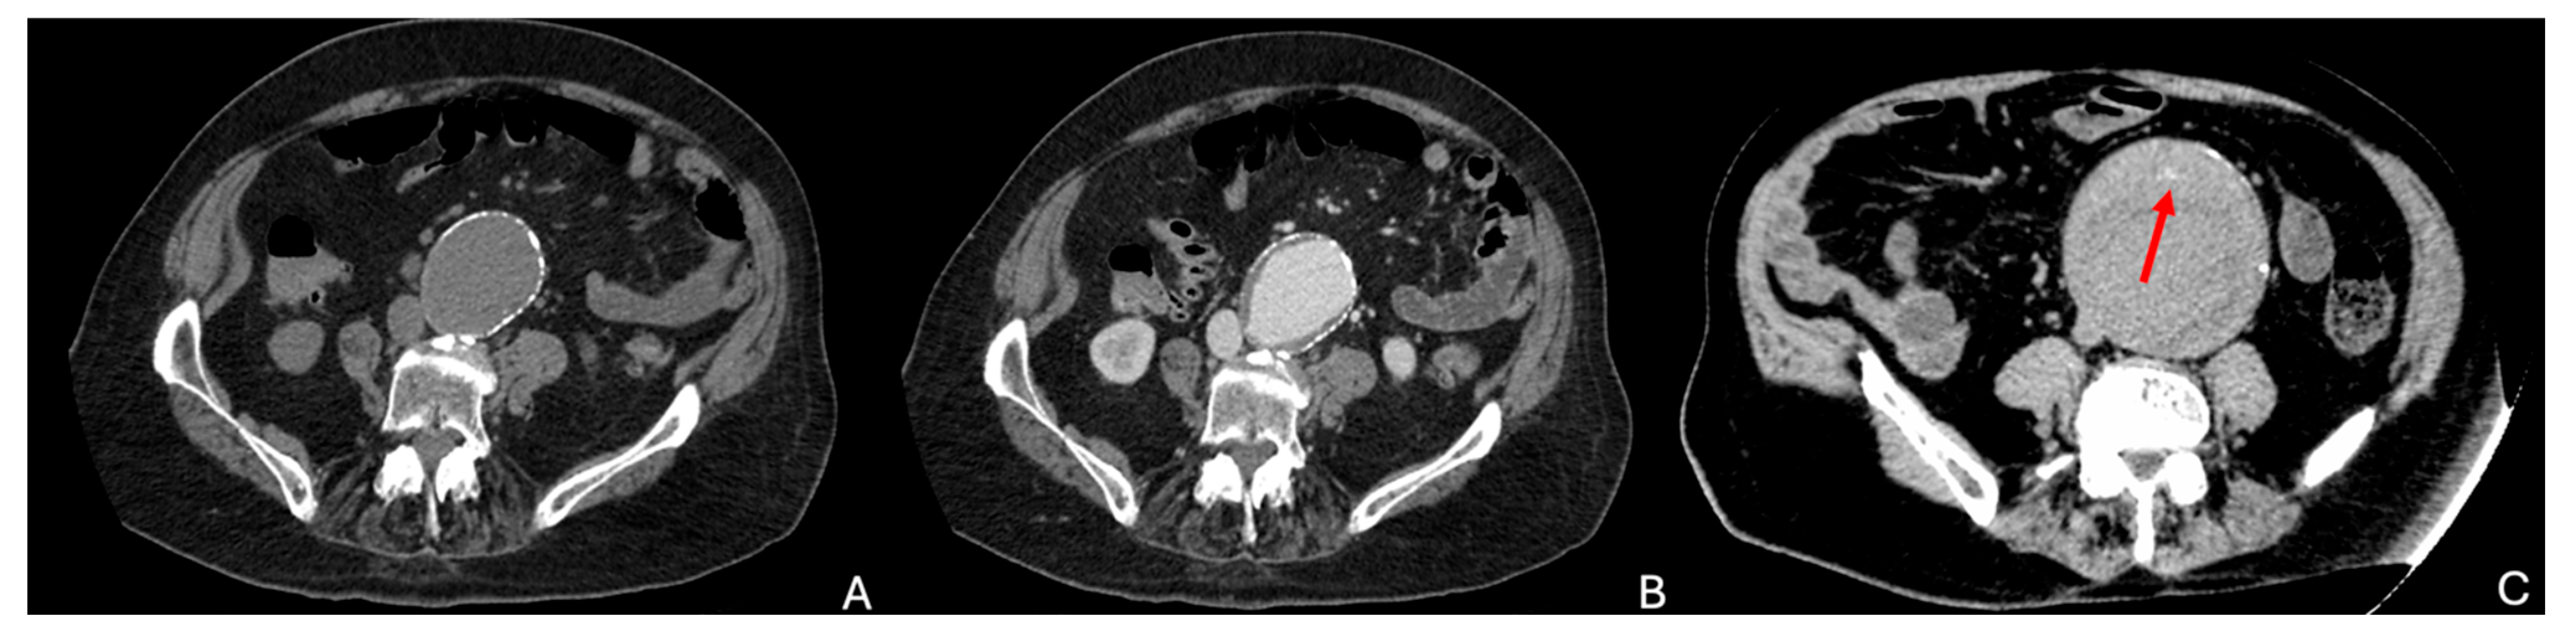

- Rakita, D.; Newatia, A.; Hines, J.J.; Siegel, D.N.; Friedman, B. Spectrum of CT Findings in Rupture and Impending Rupture of Abdominal Aortic Aneurysms. RadioGraphics 2007, 27, 497–507. [Google Scholar] [CrossRef]

- Schwartz, S.A.; Taljanovic, M.S.; Smyth, S.; O’Brien, M.J.; Rogers, L.F. CT Findings of Rupture, Impending Rupture, and Contained Rupture of Abdominal Aortic Aneurysms. Am. J. Roentgenol. 2007, 188, W57–W62. [Google Scholar] [CrossRef]

| Atherosclerotic | Typically affects older adults Male predominance | Caused by degeneration of the aortic wall, related to atherosclerosis | - Asymptomatic or symptomatic (with or without rupture) - Risk of rupture | - Dilated aorta - Mural thrombus - Wall calcifications - Crescent sign if hemorrhage in wall or thrombus - Discontinuity of the wall and contrast extravasation if ruptured - Draped aorta sign if rupture is contained or imminent rupture |